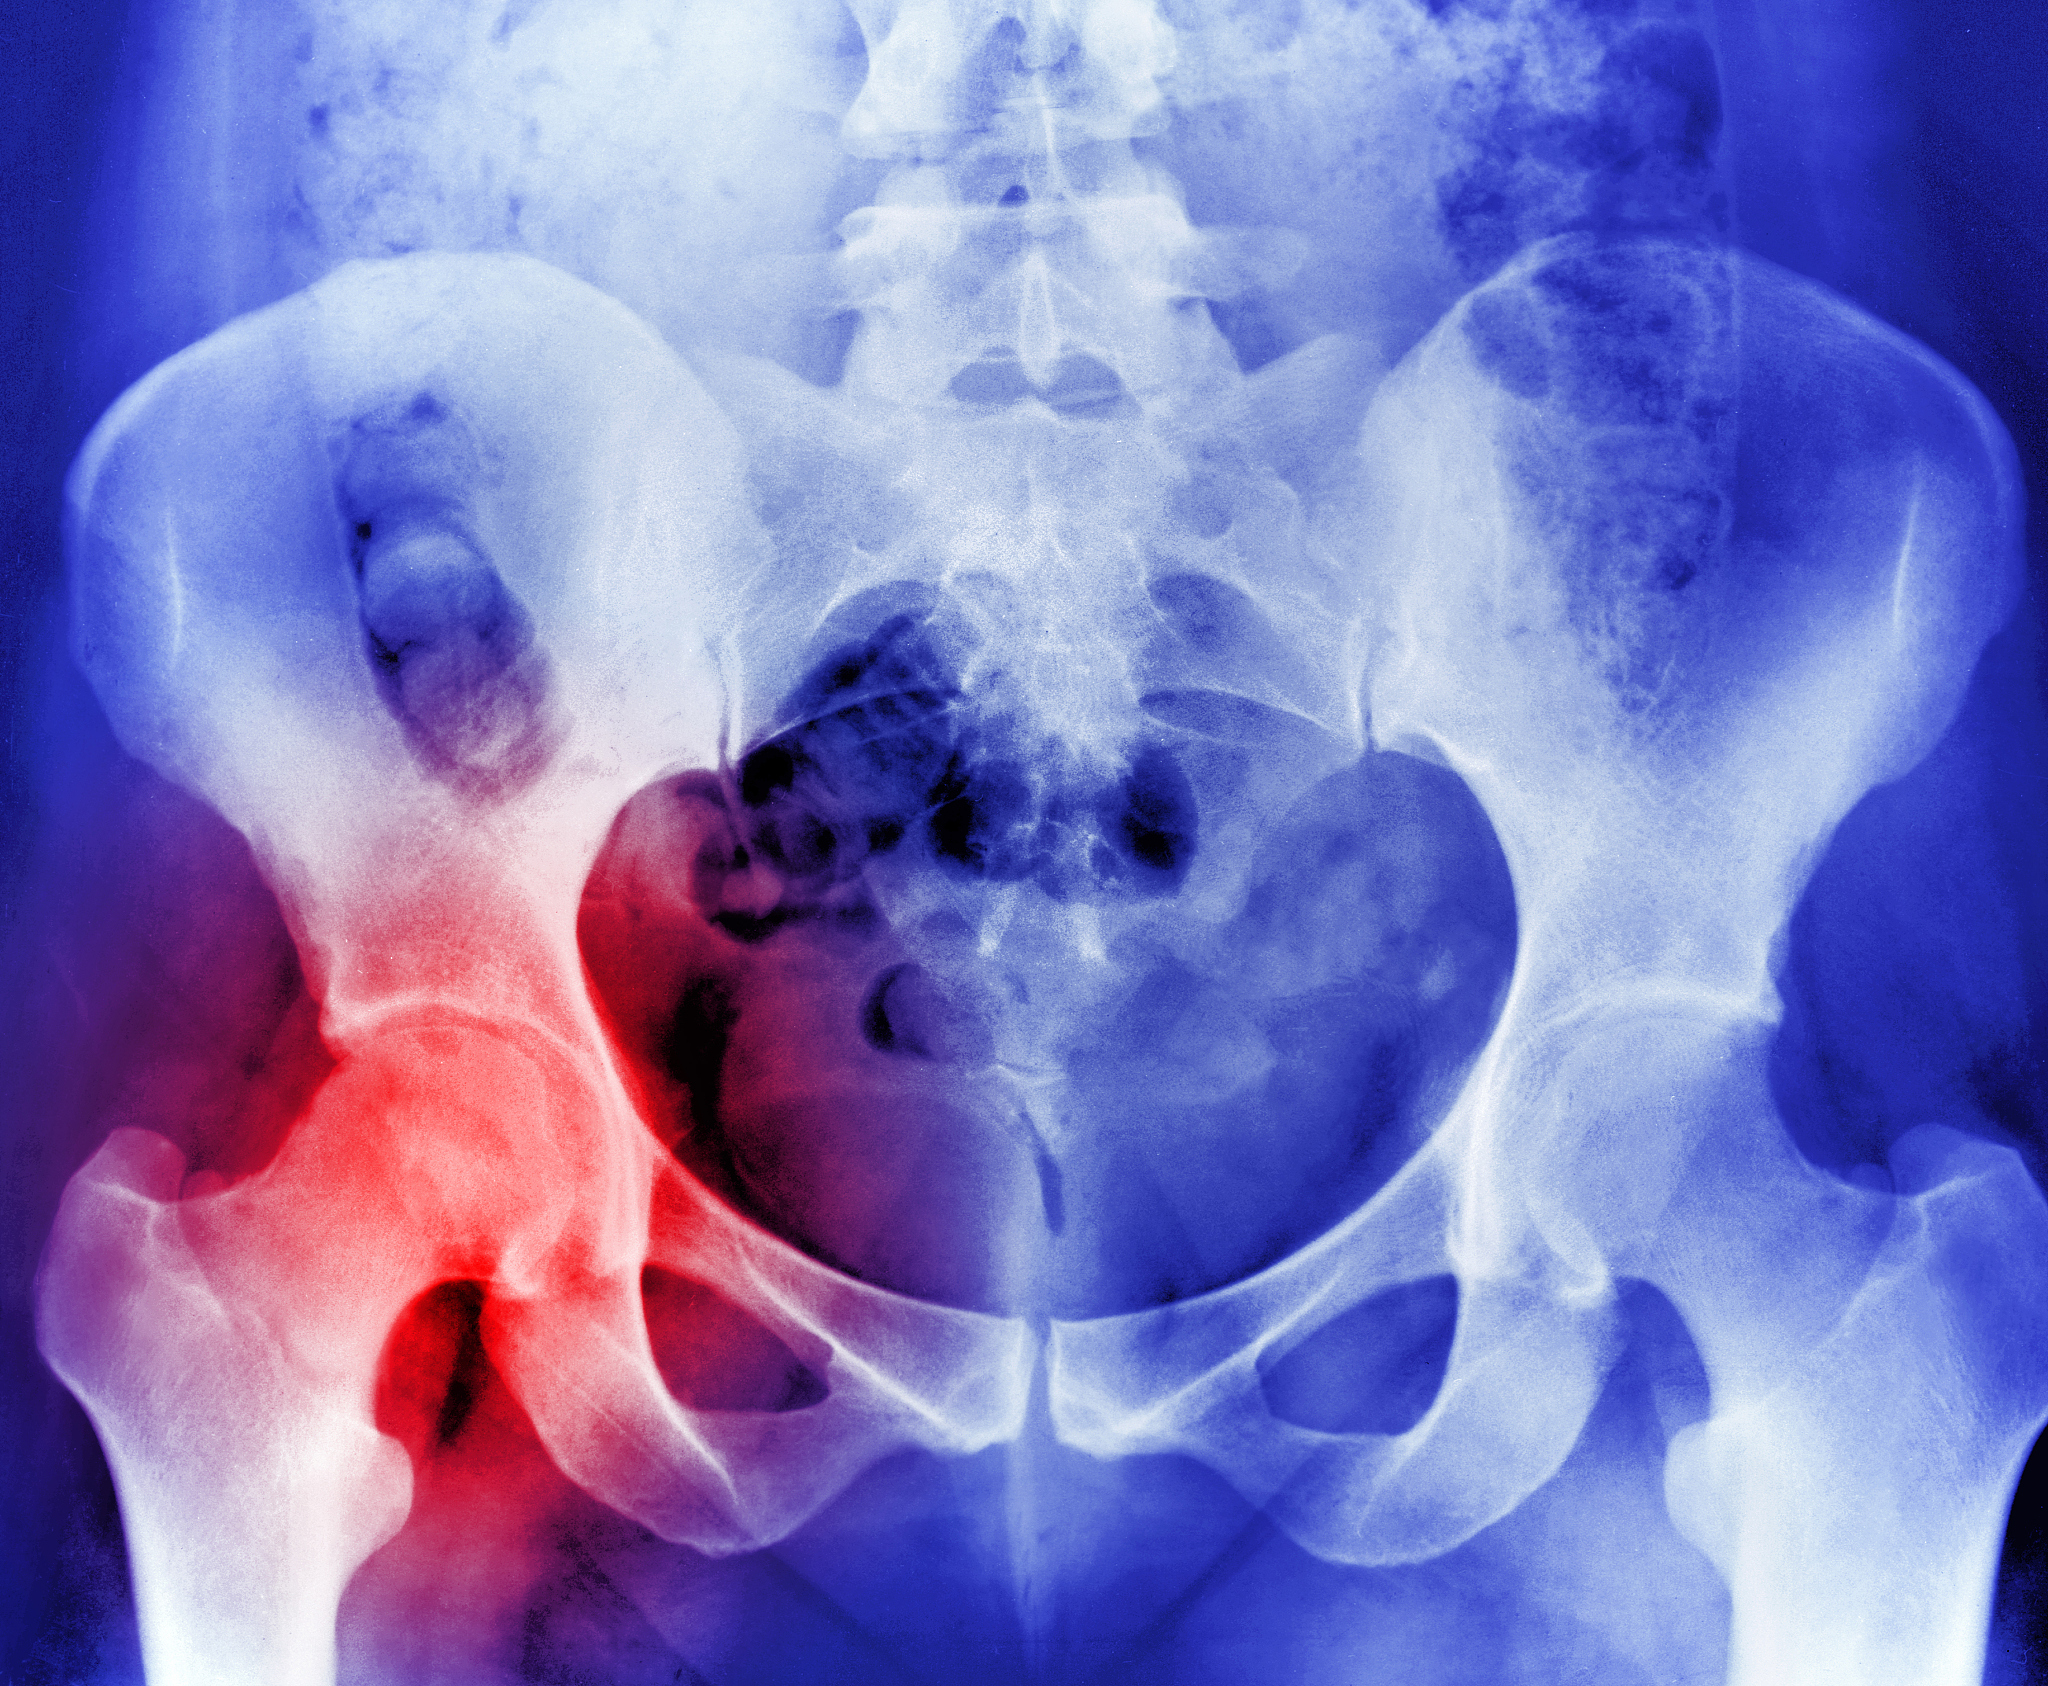

骨质疏松伴病理性骨折常见于哪些部位?

骨质疏松伴病理性骨折常发生于以下部位:

• 腰椎* 髋关节* 脊椎* 股骨颈

骨质疏松伴病理性骨折有哪些症状?

• 剧烈骨痛* 活动受限* 畸形* 脊柱弯曲